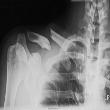

Osteoporosis

Osteoporosis is a disease that thins and weakens the bones. Your bones become fragile and break easily, especially the bones in the hip, spine, and wrist. In the United States, millions of people either already have osteoporosis or are at high risk due to low bone mass.

Osteoporosis is a silent disease. You might not know you have it until you break a bone. A bone mineral density test is the best way to check your bone health.